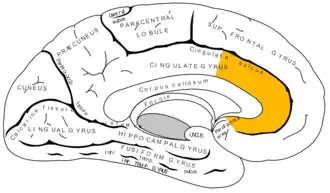

In human brains, the anterior cingulate cortex (ACC) is the frontal part of the cingulate cortex that resembles a "collar" surrounding the frontal part of the corpus callosum. It consists of Brodmann areas 24, 32, and 33.

Anterior cingulate gyrus of left cerebral hemisphere, shown in red

The anterior cingulate cortex can be divided anatomically based on cognitive (dorsal), and emotional (ventral) components.[5] The dorsal part of the ACC is connected with the prefrontal cortex and parietal cortex, as well as the motor system and the frontal eye fields,[6] making it a central station for processing top-down and bottom-up stimuli and assigning appropriate control to other areas in the brain. By contrast, the ventral part of the ACC is connected with the amygdala, nucleus accumbens, hypothalamus, hippocampus, and anterior insula, and is involved in assessing the salience of emotion and motivational information. The ACC seems to be especially involved when effort is needed to carry out a task, such as in early learning and problem-solving.[7]